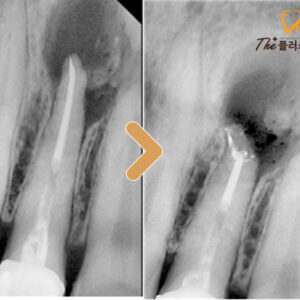

22. 울산남구치과 브릿지에 구멍이 났어요.

울산남구치과 브릿지에 구멍이 났어요.   안녕하세요. 모든 진료에 진심을 다하는 곳, 더플러스치과입니다.   치아를 잃게 되었을 때 이를 대체할 수 있는 방법으로는 임플란트나 브릿지, 틀니 등 다양한 방법이 있습니다.   그중에서도 브릿지는 상실된 치아의 인접한 치아를 삭제한 후 지대치로 사용하여 더보기…